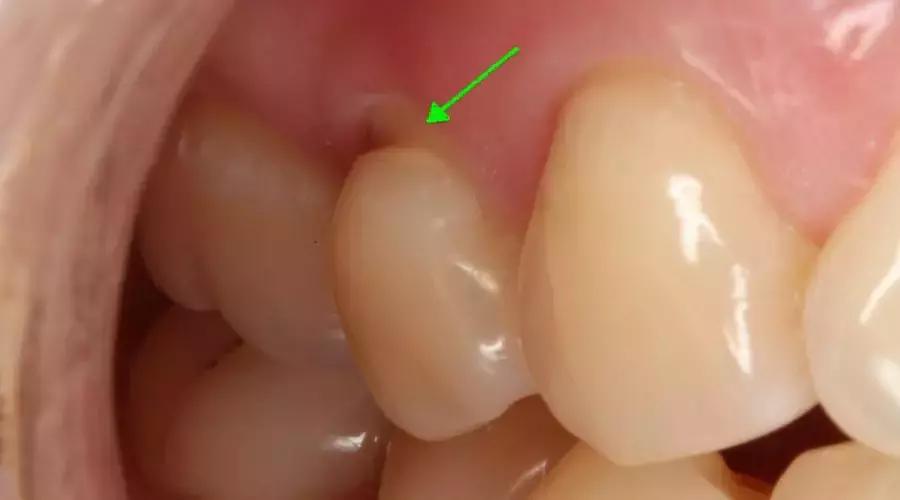

听到朋友这样的描述,当然就赶紧把他约到了诊室,大白一看这个凹槽,就赶紧拍了一张照片作为素材收集了下来。

它长这个样子:

图片由作者提供

这个「凹槽」,大白用学术说法就是「楔状缺损」(wedge-shaped defect)。

这个词语虽然看上去文绉绉的,不过其实说白了就是朋友口中的:牙齿颈部上的一道「凹槽」。因为从侧面看,这一道凹槽就是外侧宽里侧窄,像是一个「楔子」的空隙。